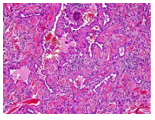

Correlation Between Peripheral Blood Cells and their Membrane Charge Depending on the Radicality of Surgical Removal of Glioblastomas

Rozumenko V, Gridina N, Khomenkova L, Khrystosenko R, Samoilov A, Kot L, Zvyagintseva T and Myronchenko S. 16(11): 01-07.